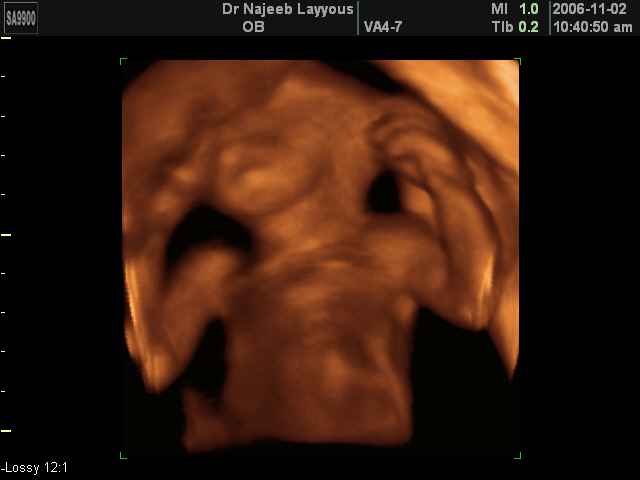

- Fetal Behavior Ultrasound Photos

Ultrasound Photos in 3D showing Fetal Behavior Inside the uterus | Dr N Layyous